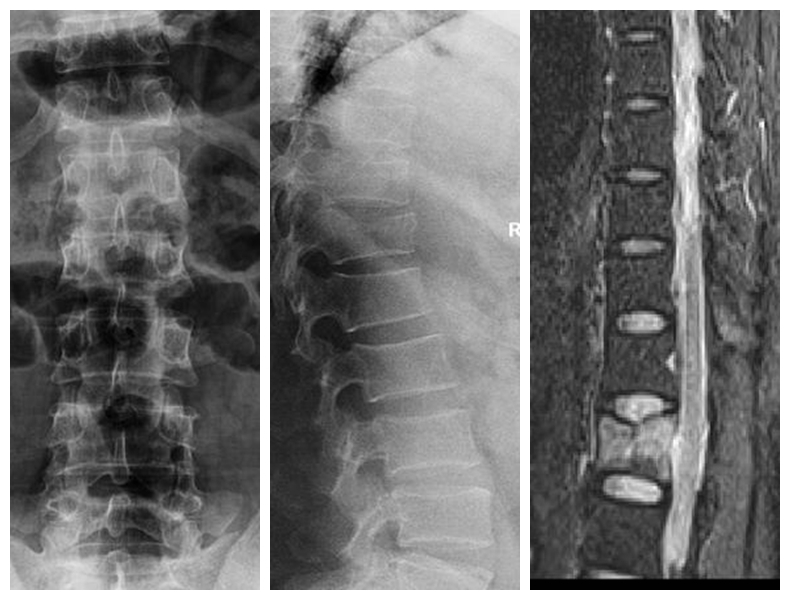

经皮胸腰椎骨折椎弓根螺钉内固定技术

传统胸腰椎骨折切开复位椎弓根螺钉内固定术组织创伤大、失血量大、住院时间长、下地时间晚、费用高。经皮胸腰椎骨折椎弓根螺钉内固定技术组织创伤小、失血少、住院时间段、下地时间早、费用低。

典型病例:患者**,男性,43岁,因“摔伤致胸腰背部疼痛、活动受限2小时”门诊平车入院。双下肢肌力、感觉及肌张力正常。

本例患者术后5天在腰围保护下独立下床,双下肢肌力感觉正常。